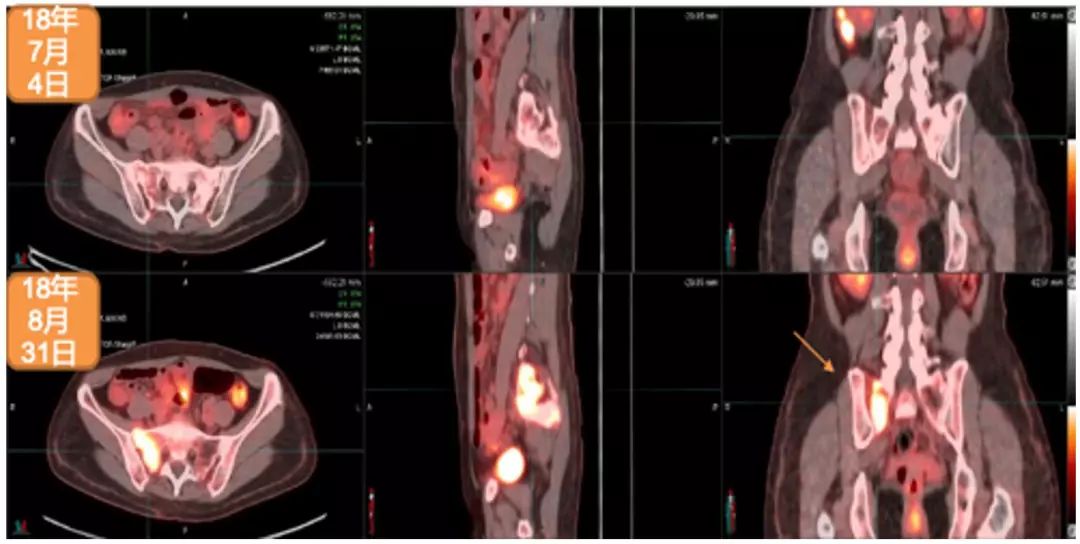

2018年5月,出现全身状况下降。2018年6月28日,进行脑部MRI检查:多发脑转移,右额叶最大病灶达2.5cm。2018年7月4日,进行PET/CT检查:多发纵隔淋巴结、胸腔和骨转移。2018年7月5日,进行右髂骨活检:转移性腺癌,原发于乳腺(BRST2+),ER-,PR-,HER2++,FISH+,Ki67:20%。

2018年7月12日至2018年7月25日期间,进行姑息性海马保护性全脑照射:30Gy,10次分割 。2018年6月15日开始姑息性TDM-1(Kadcyla®)200mg治疗。2018年12月7日,进行第8个周期治疗。2018年8月30日,进行脑部MRI检查:疾病缓解,右额叶最大病灶缩小至1.12cm。2018年8月31日,进行PET/CT检查:疾病缓解,包括胸腔积液缓解、肺原发灶、淋巴结和骨转移灶缩小并被吸收。治疗过程中仅有轻度不适,未出现显著的骨髓抑制或肝炎。Hb:11.1–12.2g/L;WBC:3.01–3.57×109/L;血小板:69-79(G2)。2018年12月28日开始下一个周期治疗。

2018年7月4日与2018年8月31日PET/CT检查对比